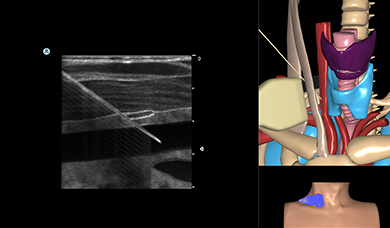

Simbionix Ultrasound Mentor is the answer to the growing need for ultrasound training among multiple medical specialties. This modular simulation platform enables easy manikin rotation (male, female, pediatric and interventional), and offers diverse applications for a range of specialties such as OB/GYN, Point-of-care Ultrasound (POCUS) and Echocardiography.

Ultrasound Mentor accelerates the development of basic to advanced technical and cognitive skills, by providing not only the probe manipulation training, but also a didactic environment enabling structured, self-guided learning including step-by-step instructions and educational aids such as 3D anatomical map and probe positioning assistant, all backed up with our progress monitoring tool MentorLearn.

Neck Module

Central Line Ultrasound Module

Pericardiocentesis Ultrasound Module

Thoracentesis Module